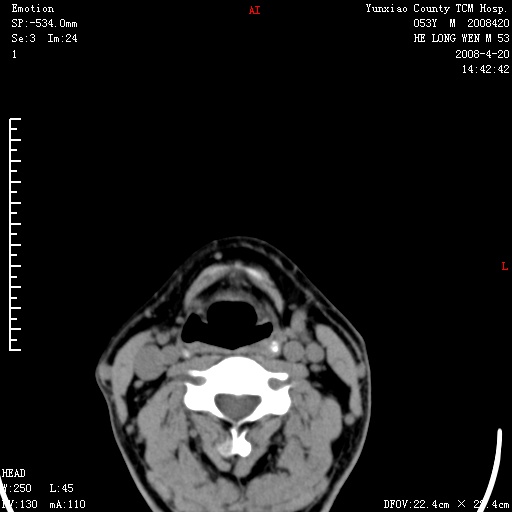

双侧扁桃体肿大:考虑化脓性扁桃体炎。

双侧扁桃体肿大 ,考虑扁桃体炎。

双侧扁桃体肿大,建议结合临床!

双侧扁桃体肿大 ,考虑扁桃体炎

应该有症状,体检此部位不是常规体检项目,支持双侧扁桃体肿大 ,考虑扁桃体炎,但还是强化一下吧。

双侧扁桃体肿大,考虑扁桃体炎,应做一下增强

显示部分为舌扁桃体,腭扁桃体未见显示。会厌显示欠规则,建议喉镜。